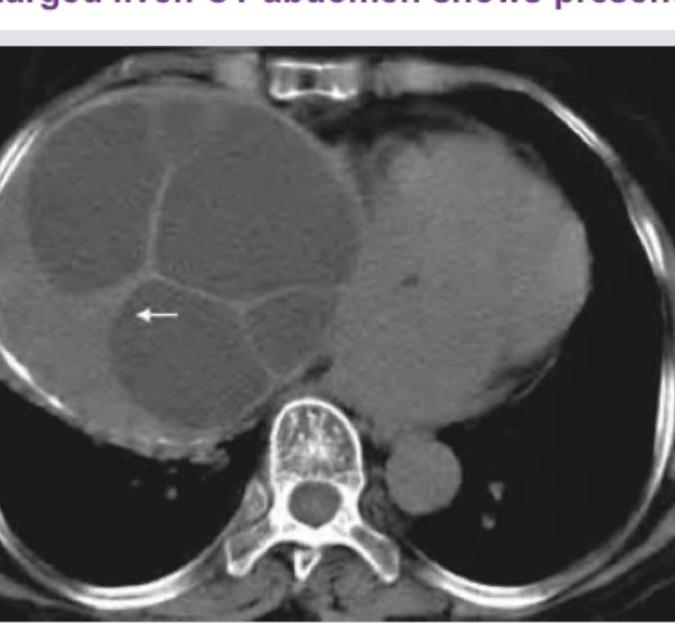

A 35-year-old shepherd presents with painless enlarged liver. CT abdomen shows presence of:

Explanation: ***Hydatid cyst*** - The patient's profession as a **shepherd** points towards exposure to dogs, which are primary hosts for *Echinococcus granulosus*, the parasite causing hydatid disease. - The CT scan shows a large, **multiloculated cystic lesion** in the liver, often referred to as "daughter cysts" or "water lily sign" due to undulating membranes within a mother cyst, characteristic of a hydatid cyst. *Amoebic liver abscess* - An amoebic liver abscess is typically a **solitary lesion**, often with a thick, enhancing rim. - It's usually associated with a history of travel to **endemic areas** and symptoms like fever, right upper quadrant pain, and elevated inflammatory markers. *Pyogenic liver abscess* - Pyogenic abscesses often present with **fever, chills, and right upper quadrant pain**, which are absent in this case. - They can be multiloculated but typically appear as **rim-enhancing fluid collections** with gas foci in some instances, not generally organized "daughter cysts." *Cavernous hemangioma* - Cavernous hemangiomas are **benign vascular tumors** that typically appear as well-defined, homogeneous hyperechoic lesions on ultrasound or enhance characteristically on dynamic CT/MRI with **peripheral nodular enhancement** followed by centripetal fill-in. - They are solid or partially cystic, but do not exhibit the **multiloculated appearance with internal septations** or daughter cysts seen in the image.